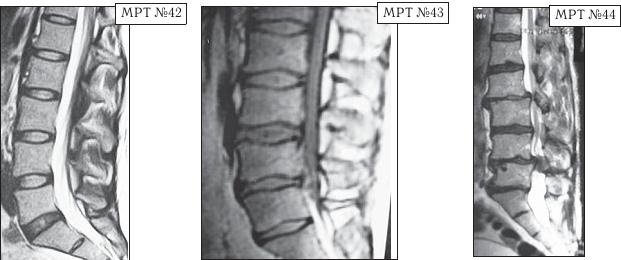

МРТ № 45

Иллюстрация к книге — Остеохондроз для профессионального пациента [i_077.jpg]

На МРТ № 45 наблюдается выраженный эпидурит.